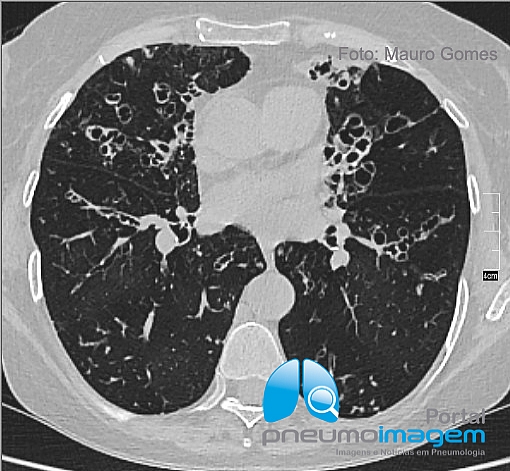

CASO CLÍNICO #49Mulher, 65 anos, asmática grave desde a infância e com exacerbações frequentes. Dosagem de IgE 1212 UI. Qual o diagnóstico mais provável? Deixe os seus comentários abaixo.

Obs: nos stories do Instagram e nos destaques do Instagram você pode ver o exame tomográfico completo da paciente.

Woman, 65, severe asthma since childhood and with frequent exacerbations. IgE 1212 IU. What is the most likely diagnosis? Give your comments below.

Note: in the stories of Instagram Instagram and highlights you can see the full CT scan of the patient.

ABPA AUMENTO DE IgE + Asma bronquiectasias centrais

BRONQUIECTASIA CILÍNDRICA BILATERAL

ABPA

Aspergilose broncopulmonar alérgica.